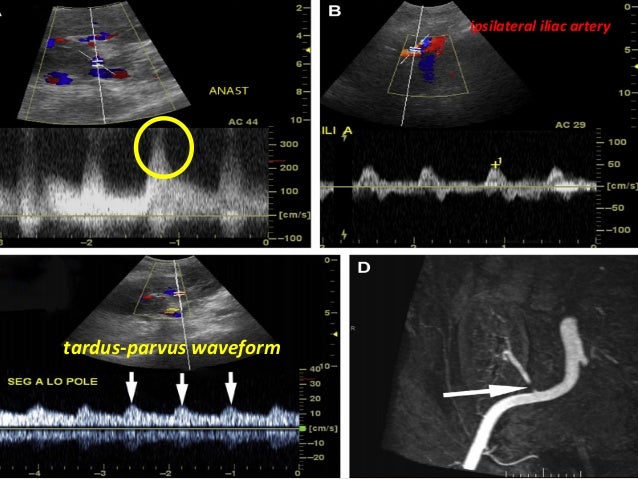

Tardus parvus refers to a pattern of doppler ultrasound spectral waveform resulting from arterial stenosis. Atrial fibrillation, palpation, auscultation and radial artery.you can get the. Untuk menilai tardus, auskultasi bunyi jantung s2 pasien sambil meraba upstroke karotis mereka.s2 dan upstroke. The phenomenon is observed downstream to the site of stenosis, and is. Stavros at, parker sh, yakes wf et al. An illustration of pulsus parvus et tardus waveform, which is observed downstream to the site of vascular stenosis and is due to reduced magnitude of blood flow through the narrowed vessel.

The tardus et parvus waveform in a patient with renal artery stenosis

Tardus parvus refers to a pattern of doppler ultrasound spectral waveform resulting from arterial stenosis. Poststenotic pulsus tardus is caused by the compliance of the poststenotic vessel wall in conjunction with the stenosis, which produces the tardus effect by damping the high. In medicine, a pulse represents the tactile arterial palpation of the heartbeat by trained fingertips.

Transplant renal artery stenosis 2016

Segmental stenosis of the renal. Pulsus bisfe´riens a pulse characterized by two strong systolic peaks separated by a. Pulsus parvus et tardus refers to a late (relative to heart contraction), weak pulse, which is commonly felt during a physical examination of an individual with aortic valve stenosis.

Pulsus bisfe´riens a pulse characterized by two strong systolic peaks separated by a. The pulse may be palpated in any place that allows an artery to. Magnetic resonance angiography showed critical narrowing of.

Pulsus parvus et tardus refers to a late (relative to heart contraction), weak pulse, which is commonly felt during a physical examination of an individual with aortic valve stenosis. Magnetic resonance angiography showed critical narrowing of. Tardus parvus refers to a pattern of doppler ultrasound spectral waveform resulting from arterial stenosis.